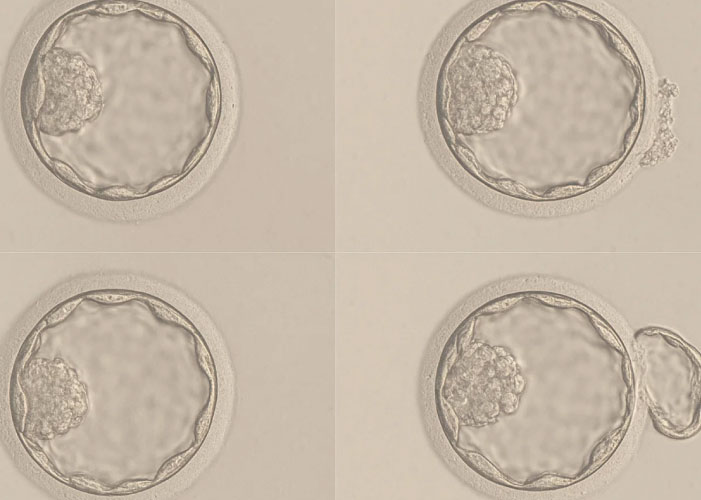

Однак перед тим, як відбудеться імплантація ембріона в слизову оболонку матки, бластоциста має самостійно звільнитися від зони пелюцида. У природних умовах цей процес відбувається автоматично: ембріон виділяє спеціальні ферменти, які поступово розчиняють оболонку, а ритмічні скорочення самої бластоцисти допомагають їй вийти назовні. Проте в деяких випадках оболонка стає занадто щільною або потовщеною, що ускладнює природне вилуплення ембріона та призводить до зниження шансів на імплантацію.

Мета процедури — створити невеликий отвір або стоншити ділянку зони пелюцида, щоб полегшити ембріону вихід. Мікроманіпуляції з ембріоном виконують в ембріологічній лабораторії під мікроскопом із застосуванням високоточного обладнання.

Виконання отвору (або стоншення) у зоні пелуцида

Ембріон поміщається в спеціальну мікроманіпуляційну систему, що фіксує його в потрібному положенні. За допомогою лазера ембріолог створює невеликий отвір діаметром від 10 до 25 мікронів, залежно від обраної тактики. Іноді замість повного отвору виконується стоншення певної ділянки. Тривалість самої лазерної маніпуляції — кілька секунд.

Спостереження за ембріоном після процедури